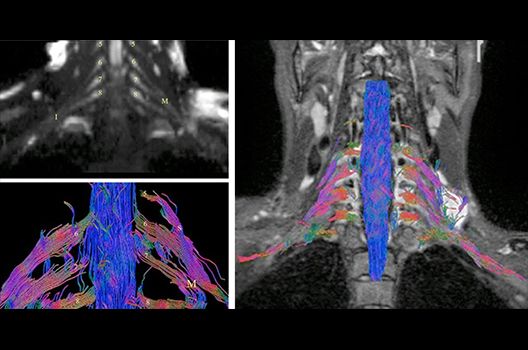

- MR-Diffusionstensorbildgebung (Faserbahndarstellung/fiber tracking)

Die Magnetresonanztomographie (MRT) ist ein Verfahren, bei dem durch magnetische Kräfte Bilder des Körperinneren angefertigt werden. In der Neuroradiologie können manchmal kleinste Veränderungen schwere Folgen haben; daher forschen wir an der Entwicklung hochauflösender MRT-Sequenzen, mit denen diese Prozesse und auch einzelne Nervenfaserbahnen sichtbar gemacht werden können. Darüber hinaus sind bei vielen Erkrankungen des Gehirns die Blutgefäße betroffen. Daher arbeiten wir an der Neu- und Weiterentwicklung von MRT-Sequenzen zur Darstellung der Blutgefäße und zur Blutflussanalyse (sog. „Angio-MRT“). Einen besonderen Forschungsschwerpunkt unserer Klinik stellen die MR-Protonenspektroskopie und die funktionelle MRT dar, mit denen die Analyse einzelner chemischer Substanzen im Hirngewebe oder die Darstellung ausgewählter Hirnfunktionen möglich ist.